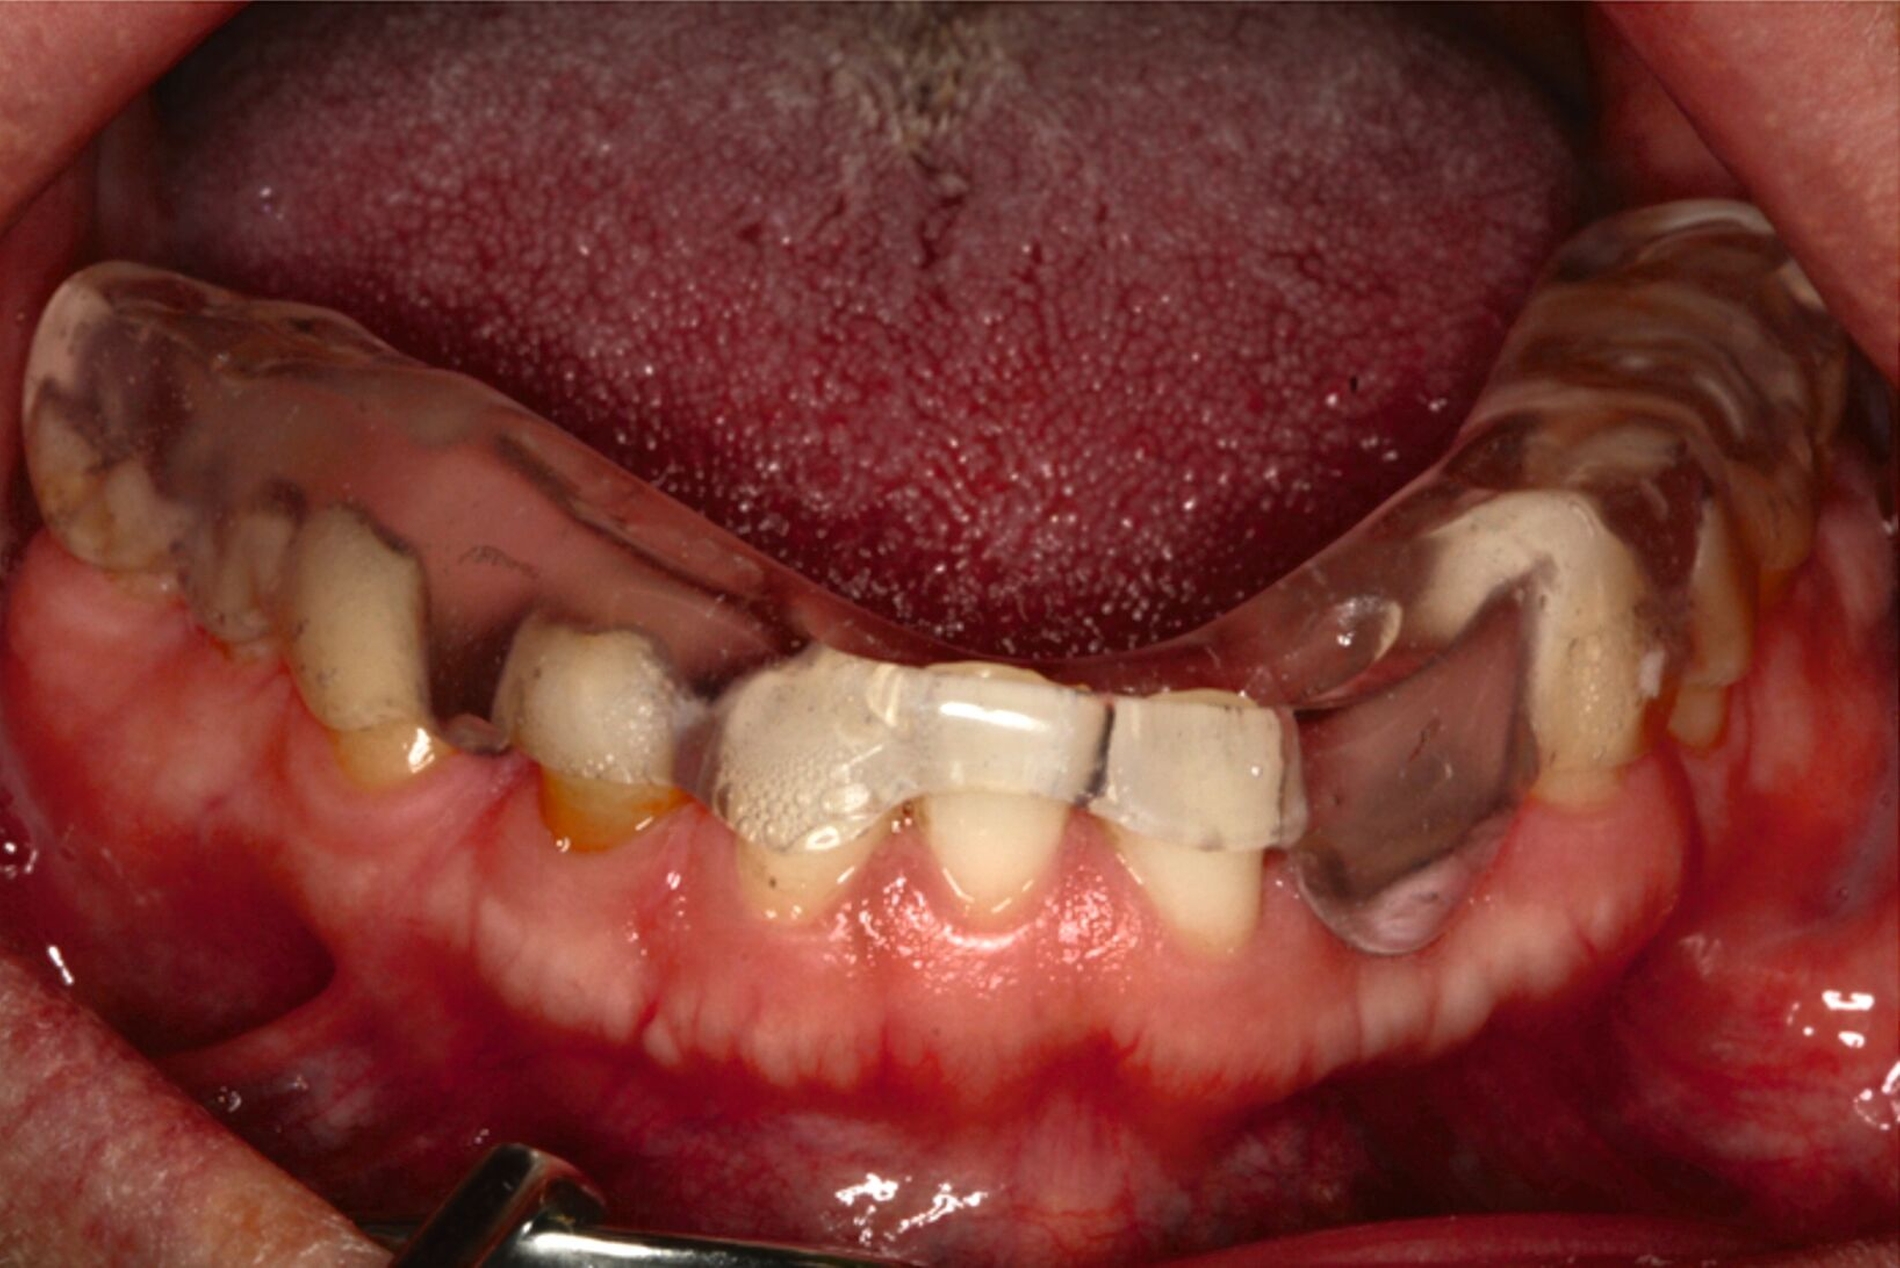

Ein 30-jähriger Patient stellte sich mit multipler Oligodontie (15 fehlende bleibende Zähne), Persistenz von Milchzähnen sowie ausgeprägter Dysgnathie mit progenem Deckbiss vor. Klinisch zeigten sich hypoplastische Restzähne, Fehlstellungen und erhebliche funktionelle Beeinträchtigungen (Abbildung 1). Sein Wunsch bestand in einer möglichst optimalen ästhetischen und funktionellen Versorgung seiner für ihn äußerst unbefriedigenden Gebisssituation. Die molekulargenetische Analyse bestätigte eine homozygote Mutation im WNT10A-Gen als Ursache der Zahnagenesie.

Eine mögliche und indizierte Umstellungsosteotomie wurde vom Patienten abgelehnt. Da seitens des Patienten eine Kopfbissstellung möglich war, wurde eine Bissumstellung und -hebung mit nur noch geringgradigem Vorbiss und anschließender Zahnimplantation in Erwägung gezogen. Begonnen wurde mit einer temporären Schienentherapie zur Neuorientierung der Bisslage (Abbildung 3). Da der Patient die angepasste Bisshebung tolerierte, wurde diese nach Entfernung der persistierenden Milchzähne 55, 53, 52, 62 und 83 temporär mittels einer Valplastprothese (Abbildung 4) als Interimsersatz im Oberkiefer gesichert.